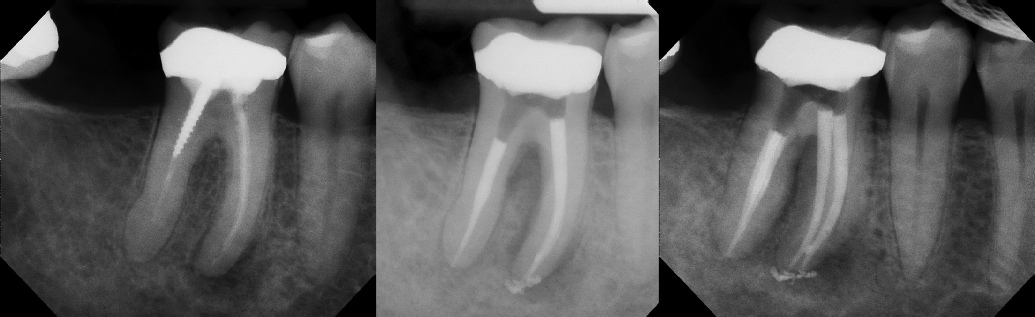

Root Canal Retreatment - Meriden 8 mos. recall Post-op Pre-op